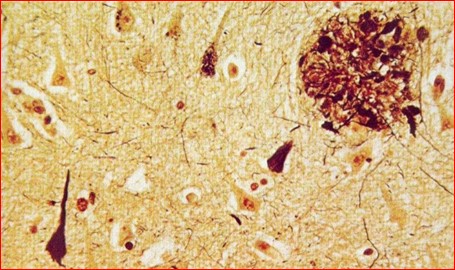

L’examen microscòpic demostra una atròfia de la cortical i la presència de plaques de substància amiloide amb degeneració neuronal (Fig.3). El 1906, presenta el cas en una conferència en el marc d’una reunió de psiquiatres, on hi assistia Jung, amb el títol “Una nova malaltia greu característica de l’escorxa cerebral”, però no va despertar gaire interès. L’any següent publica el cas juntament amb el seu cap, el professor Kaepelin, que és qui donarà el nom de malaltia d’Alzheimer a aquest procés en el seu Manual de Psiquiatria, publicat el 1910.